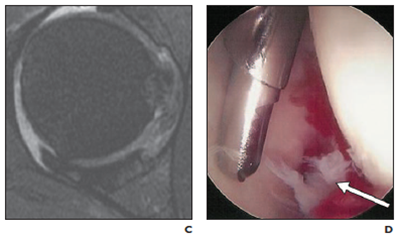

So how do we diagnose ligamentum teres pathology? The correlation between MRI and ligamentum teres damage is poor, with one study finding only 4% of tears were identified on MRI pre-operatively (Botser et al, 2011). MR Arthrograms (a series of MRI's performed after injection of a contrast medium) are often poor, with a study finding only 2 of 23 ligamentum teres ruptures were identified on MR Arthrogram (Bardakos & Villar, 2009). Another study in 2012 compared 116 scans, with radiologists with 10+ years experience diagnosing a maximum of 8 out of 12 tears, however falsely recording up to 26 intact ligaments as having tears, so poor specificity (Blankenbaker, De Smet, Keene, & Del Rio, 2012).

Arthroscopes are the gold standard in detecting ligament pathology. Previously not many arthroscopes reported a ligamentum teres tear (Bardakos & Villar, 2009; Cerezal et al., 2010), but as arthroscopes are becoming more routine, and technology is improving, now 51% of arthroscopes show some damage where previously only full thickness tears were reported (Botser et al., 2011).

MRI Arthrogram (fraying at 3 o'clock) Arthroscope

Interestingly, the presence of ligamentum teres tears were correlated with increased labral tear size and higher grade chondral damage (p=0.005) than those with intact ligaments (Botser et al., 2011). Another study in 2012 found all full ligamentum teres tears had a co-existing FAI and/or labral damage (Martin et al., 2012). It appears ligamentum teres pathology co-exists with other hip pathology.